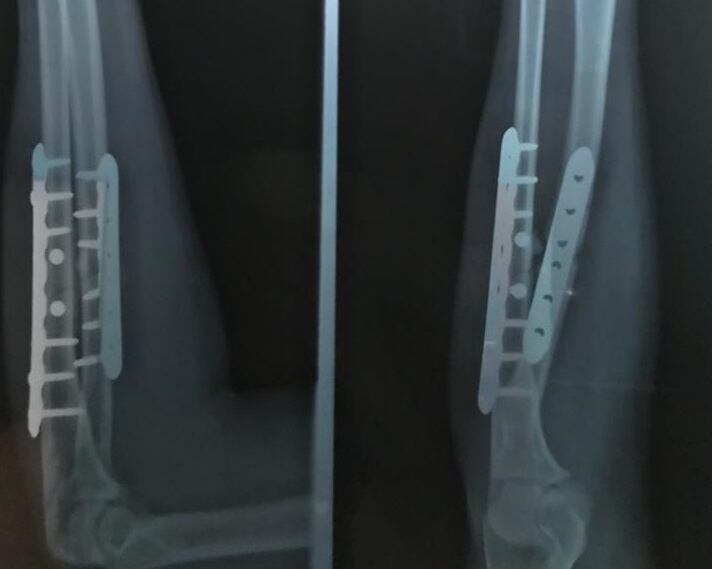

La guardameta de 24 años se quebró el antebrazo (fractura de radio y cúbito) el 5 de octubre, durante el Premundial femenino. Los gritos de dolor dejaron en evidencia que se trataba de algo grave.

Dos placas y 14 pines son su mayor recuerdo de la primera operación a la que se ha tenido que someter en su carrera.